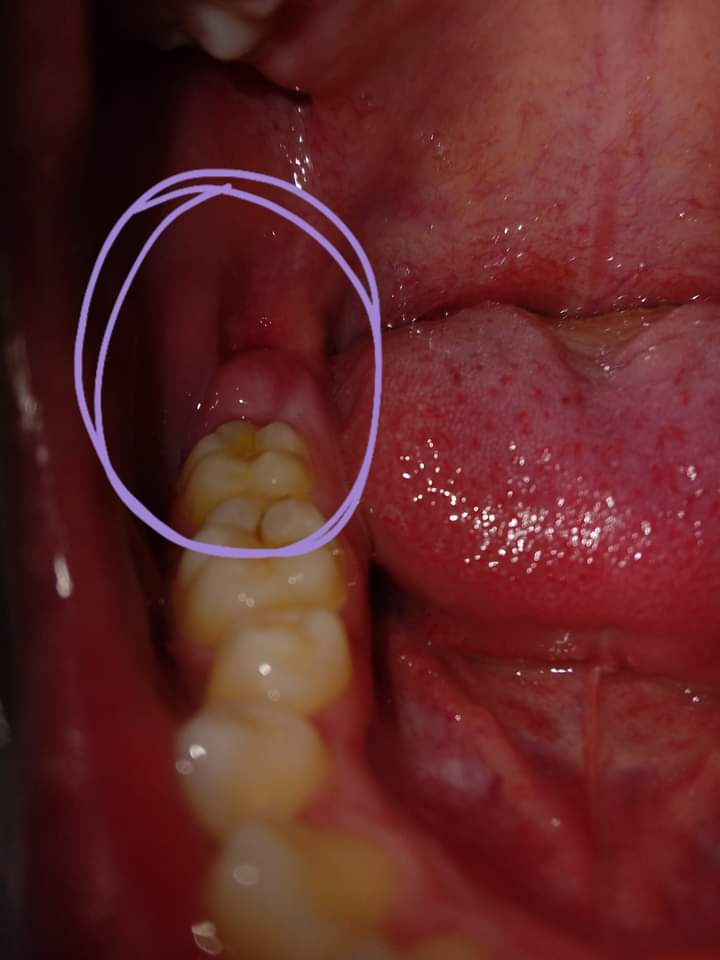

Em có nhổ răng khôn vào hồi t2.Sau 1th thì gần vị trí răng khôn đã nhổ có xuất hiện 1 nốt phồng ,khi ấn vào thì thấy có dịch màu ngà vàng chảy ra.Em cs súc miệng nc muôia thì có thấy nốt đó teo dần.Nhưng hôm sau cx ở vị trí răng khôn cs 1 nốt nhỏ mọc lên nốt này thì lại cứng,nhỏ.Với tình trạng lợi của e dạo này rất mỏng,có thể thấy đc luôn cả xương or hàm răng.Kbt đây là tình trạng gì nhờ bác sĩ giải đâp ạ.

Cái nốt phồng trong ảnh bây h bé lại rồi nm lại mọc 1 nốt mới ở gần đó nốt này cứng và chắc hơn nốt phồng này( nốt phồg này mềm ko đau ko cứng có dịch ngà vàng) thì bị sao ah